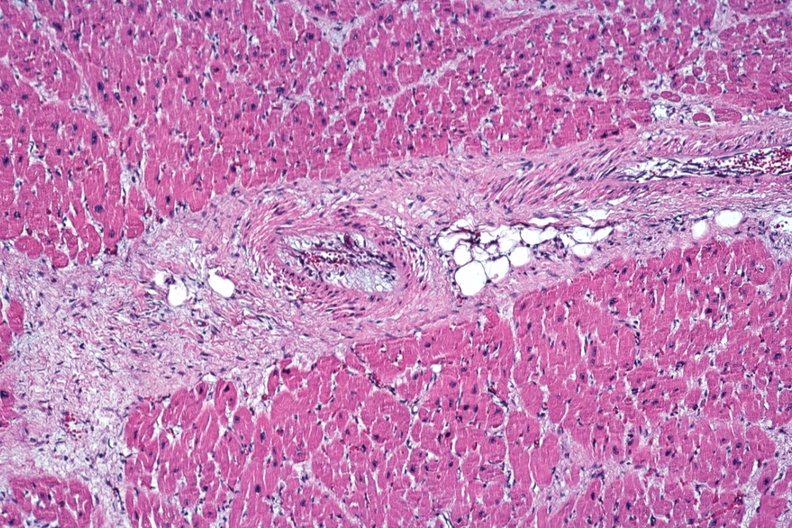

HISTOLOGY: CARDIOVASCULAR: HEART: Cocaine Abuse: Micro med mag small artery in myocardium with marked intimal thickening questionable evidence of previous injury due to spasm woman in twenties sudden death